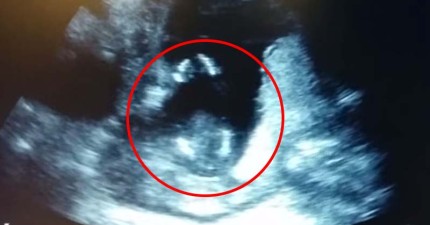

這個還在肚中的寶寶,竟然在超音波檢查時跟爸媽超溫馨一拍一唱!